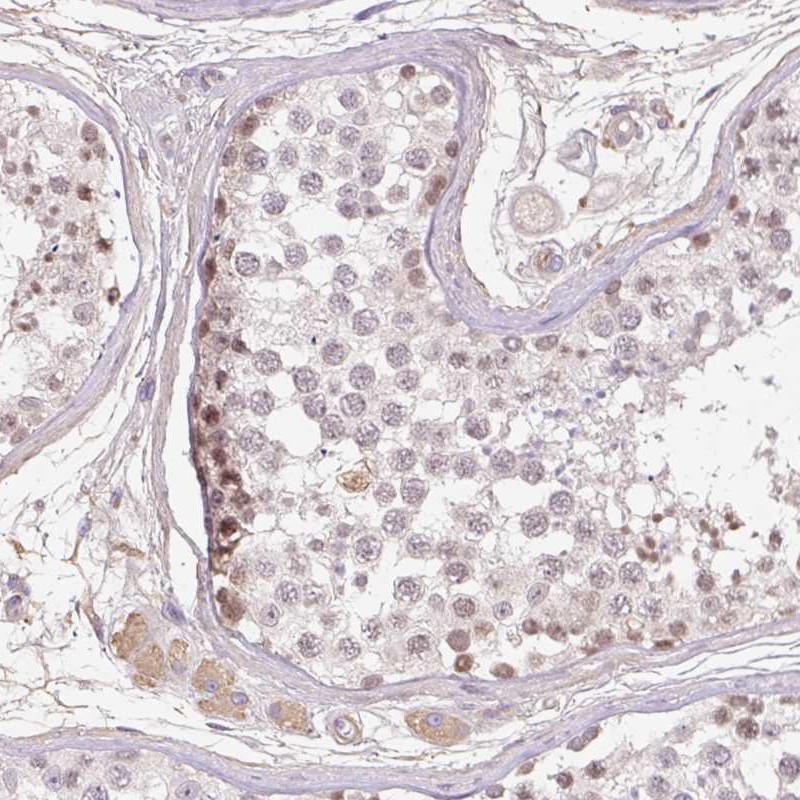

Immunohistochemical staining of human testis shows moderate nuclear positivity in a subset of cells in seminiferus ducts.